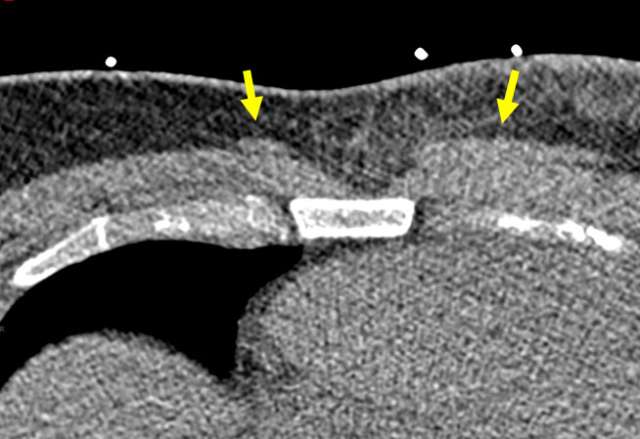

Case Sternalis Muscle Figure 1

Non-contrast CT of the chest shows bilateral sternalis muscles superficial to the pectoralis major. The left sternalis muscle is larger than the right. Subcutnaeous fat stranding and skin thickening in the left pectoral region is infectious/inflammatory and unrelated to presence of sternalis muscles.